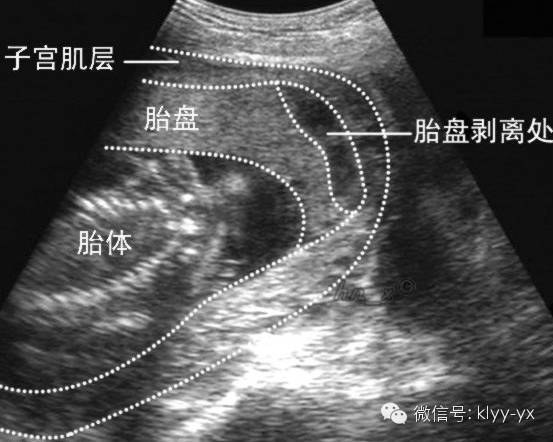

容易出现妊娠期高血压、胎盘早剥、流产、早产等;